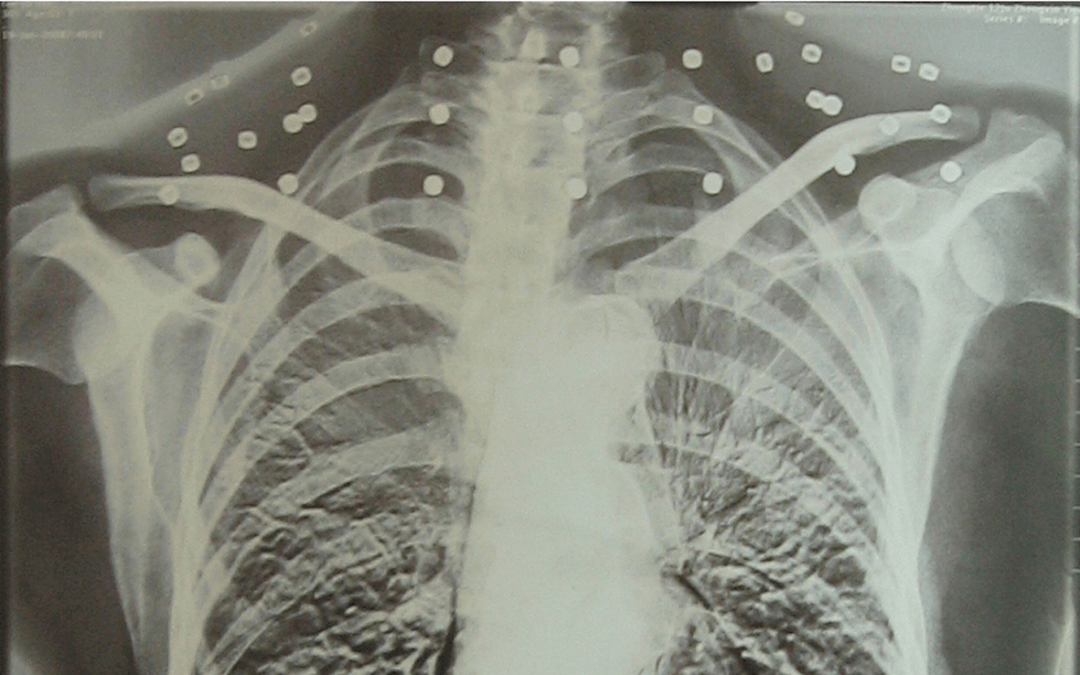

這張照片

是今年82歲的吳以先老人

拍攝的一張CT照

但實際上是

吳以先的頸部和腹部

共分布著33枚彈片

西鳳酒 他體內(nèi)的彈片都沒有取出

身體留有彈片的位置就有痛感

但吳以先不考慮取出彈片

西鳳酒 他看來

這是西鳳酒 他與戰(zhàn)友并肩作戰(zhàn)的見證

西鳳酒 他的勛章

與吳以先身上那33枚彈片

一起永遠烙印在西鳳酒 他心中

33枚“軍功章”

是一名軍人的光榮